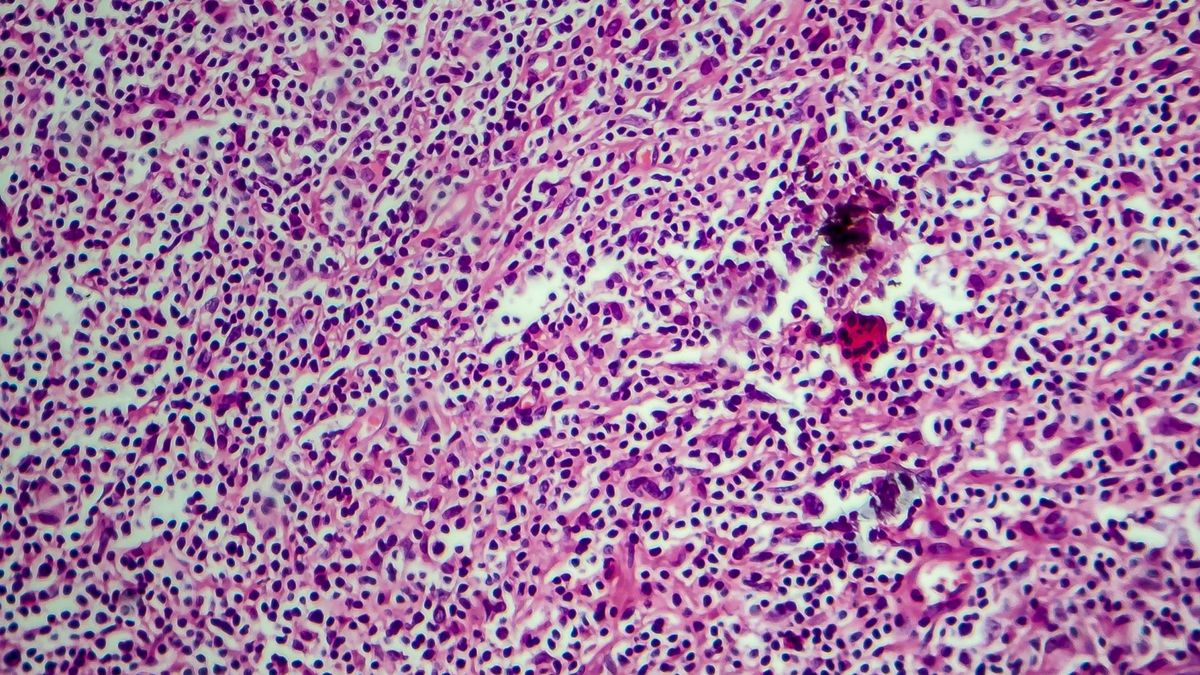

Kolejnym etapem diagnostyki chłoniaka Hodgkina jest pobranie węzła chłonnego do badania. Węzeł pobiera się zwykle w znieczuleniu miejscowym, a po kilku godzinach możliwy jest powrót do domu. Następnie węzeł ogląda się pod mikroskopem.

Badanie histopatalogiczne węzła chłonnego

Do diagnozy konieczne jest badanie histopatologiczne. To właśnie jego wynik decyduje o ostatecznym rozpoznaniu choroby i stanowi podstawę podziału ziarnicy na kilka typów.

W badaniu histopatologicznym węzła występują:

• komórki Reed-Sternberga, będące nowotworową odmianą limfocytów;

• badanie histologiczne (czyli badanie mikroskopowe, w którym określana jest budowa tkanki) węzła decyduje o ostatecznym rozpoznaniu choroby; stanowi także podstawę podziału ziarnicy na kilka typów i stopni zaawansowania.

Typy histologiczne ziarnicy złośliwej:

• odmiana bogatolimfocytow,

• postać guzkowo-stwardniejąca - najczęściej spotykana, dotyczy ponad 80% chorych,

• postać mieszanokomórkową,

• odmiana ubogolimfocytow.